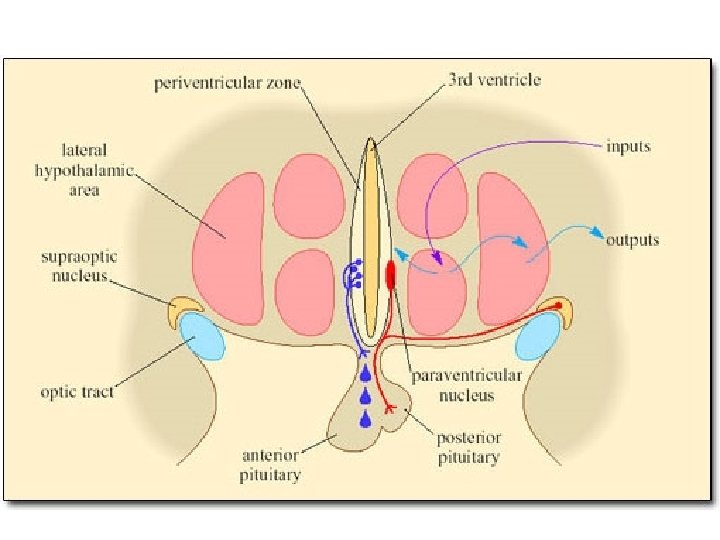

Hypothalamus – funkce Hypothalamus • ncl. suprachiasmaticus – centrum cirkadiálních rytmů • ncl. supraopticus + paraventricularis (magnocelulární neurony) – ADH (vazopresin) + oxytocin • ncl. arcuatus (infundibularis) a okolí (parvocelulární neurony) – statiny a liberiny • ncl. tuberomamillaris – histamin do mozku a míchy („arousal“) • aktivován orexinem z lat. hypothalamu • nedostatek při narkolepsii

Přední hypotalamus • ncl. paraventricularis – oxytocin, ADH • ncl. supraopticus – oxytocin, ADH • ncl. preopticus medialis – pokles tlaku a tepu • ncl. hypothalamicus anterior – termoregulace, pocení, inhibice TSH • ncl. suprachiasmaticus – cirkadiánní rytmus

Hypophysis (Pověsek) • adenohypophysis (= lobus anterior) – vývoj z Rathkeho výchlipky ze stropu hltanu – hormony (ACTH, TSH, FSH, LH, STH, MSH) – ovlivněna hypotalamickými releasing a inhibiting hormony – transport z ncl. arcuatus přes tractus tuberoinfundibularis (= neurokrinie) → hypotalamo-hypofyzoportální systém – Sheehanův syndrom • neurohypophysis (= lobus posterior) – – – vývoj jako výchlipka diencephalon nucleus supraopticus (vazopresin = ADH) ncl. paraventricularis (oxytocin) axonální transport z hypotalamu reaguje na změnu osmolality přes organum subfornicale et vasculosum laminae terminalis (chybí HE bariéra)